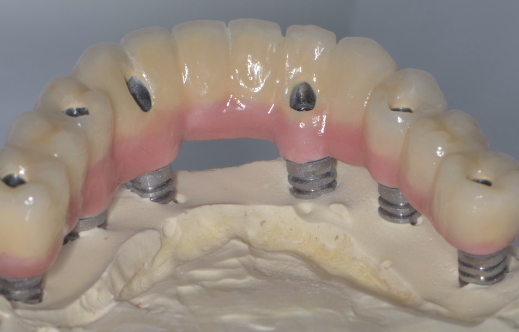

După acest interval lucrarea provizorie se îndepărtează, în fiecare implant se montează câte un dispozitiv necesar realizării amprentelor (Fig. 3.6.7) care vor servi tehnicianului dentar pentru realizarea punții definitive (Fig. 3.6.8 și Fig. 3.6.9). Realizarea acesteia se face în câteva zile, interval în care pacientul va continua să poarte lucrarea provizorie realizată inițial.

Lucrarea finală se va înșuruba pe componentele protetice ale implanturilor (Fig. 3.6.10 și 3.6.11), iar perforațiile de acces pentru șuruburi (Fig. 3.6.12) vor fi acoperite cu material compozit (Fig. 3.6.13). După fixarea definitivă (Fig. 3.6.14) puntea poate fi oricând detașată de către medicul dentist la nevoie, prin simpla îndepărtare a materialului compozit și desfiletarea șuruburilor de fixare.